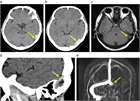

1. 脳静脈血栓症はCTやMRIにて診断を行う。特に、MRIのT2*強調画像Susceptibility-Weighted ImageSWIとMRV(magnetic resonance venography)、あるいはCTV(CT venography)でまず診断を行い、必要に応じて脳血管造影を行うことが推奨される(推奨度1)